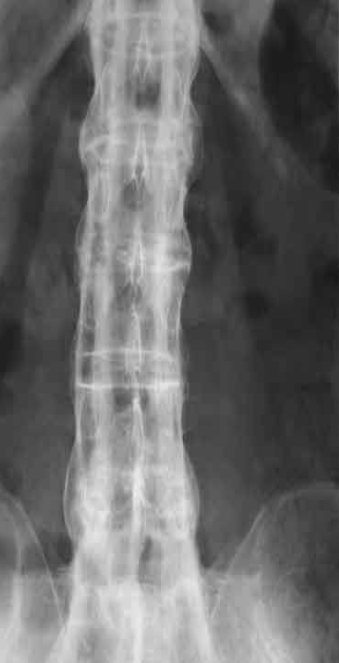

Rugger jersey spine’ (renal osteodystrophy

Bamboo spine | Ankylosing spondylitis

A. Give the name of the used imaging modality. B. What name is given to this appearance of the spine?

A. ONE radiological manifestation for marked abnormality.

Increased density and coarse trabeculae in the wider than the normal vertebral bodies (arrows)

B. Identify the most likely cause of the abnormal vertebrae shown Paget’s disease